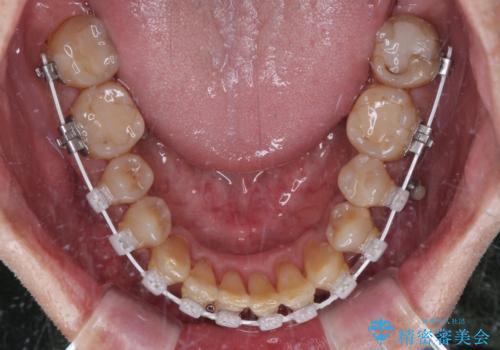

- 矯正装置

- 審美装置

- 1年10ヶ月

クロスバイト改善には難儀しましたが、咬みやすく、笑ったときに清潔感ある口元に仕上げることができました。